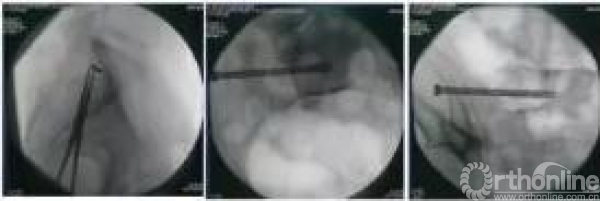

X线监视下骶骨骨折经皮微创骶骨拉力钉内固定术+髂骨翼和髋臼骨折经皮微创空心螺钉内固定术(全麻)。

各种术中透视体位的应用(十余种,适当组合)

骨盆正位、入口位、出口位、闭孔斜、髂骨斜、LC-2长轴位、闭孔出口位、髂骨入口位、骶髂关节正位入口位、髂骨翼正位、骶髂关节正位出口位、泪滴位、骨盆侧位等。

本患者操作要点

单侧骶髂螺钉

骨盆侧位

骨盆入口位

骨盆出口位

髂骨翼螺钉

髂骨斜位

髂骨翼顶视位

LC-2螺钉

泪滴位